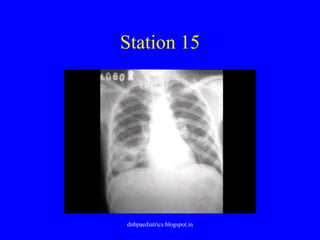

Station 15

• This 7 year old child was diagnosed as

acute pneumonia on the basis of clinical

profile, neutrophilic leucocytosis and chest

x-ray – was treated with IV Ceftriaxone

• 4 days later, as fever continued, repeat CBC

and chest x-ray were ordered

• What is the problem?